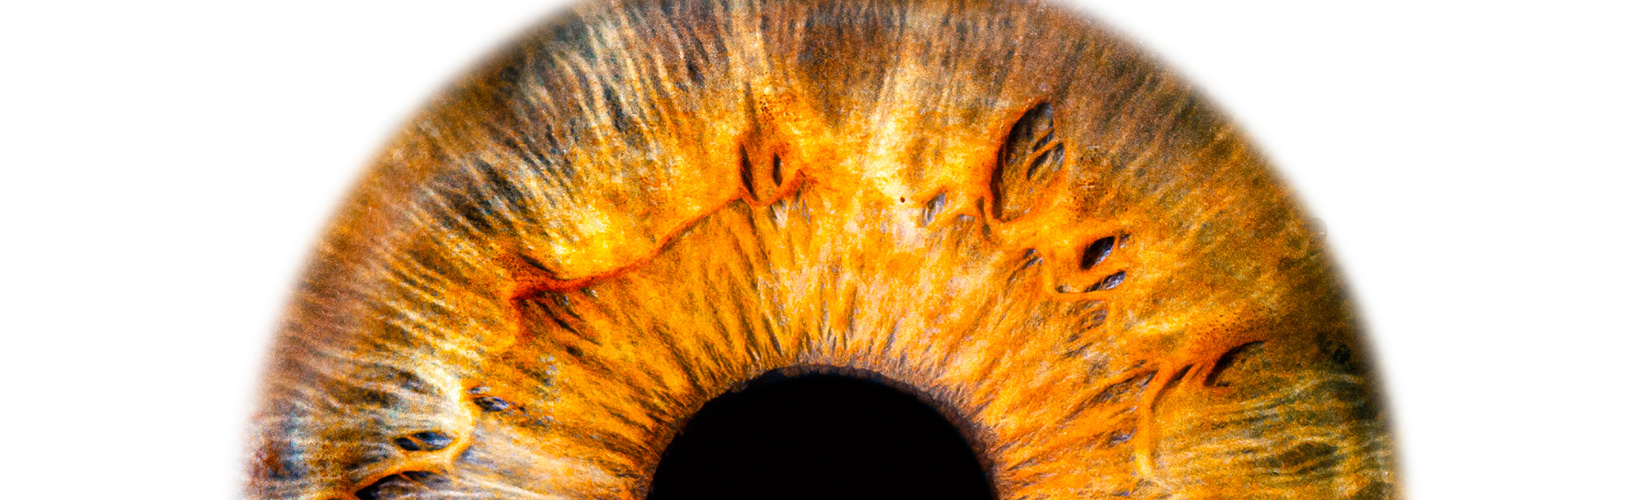

Iridodialysis refers to a separation of the iris from the ciliary body at the iris root. It can be post-traumatic or iatrogenic. Small iridodialysis, especially if covered by the upper lid, may be ignored, but larger dialysis can cause visual symptoms such as glare, photophobia, and monocular polyopia. It also causes polycoria and often results in a displaced pupil. In light-coloured irides, it causes cosmetic concerns as well.